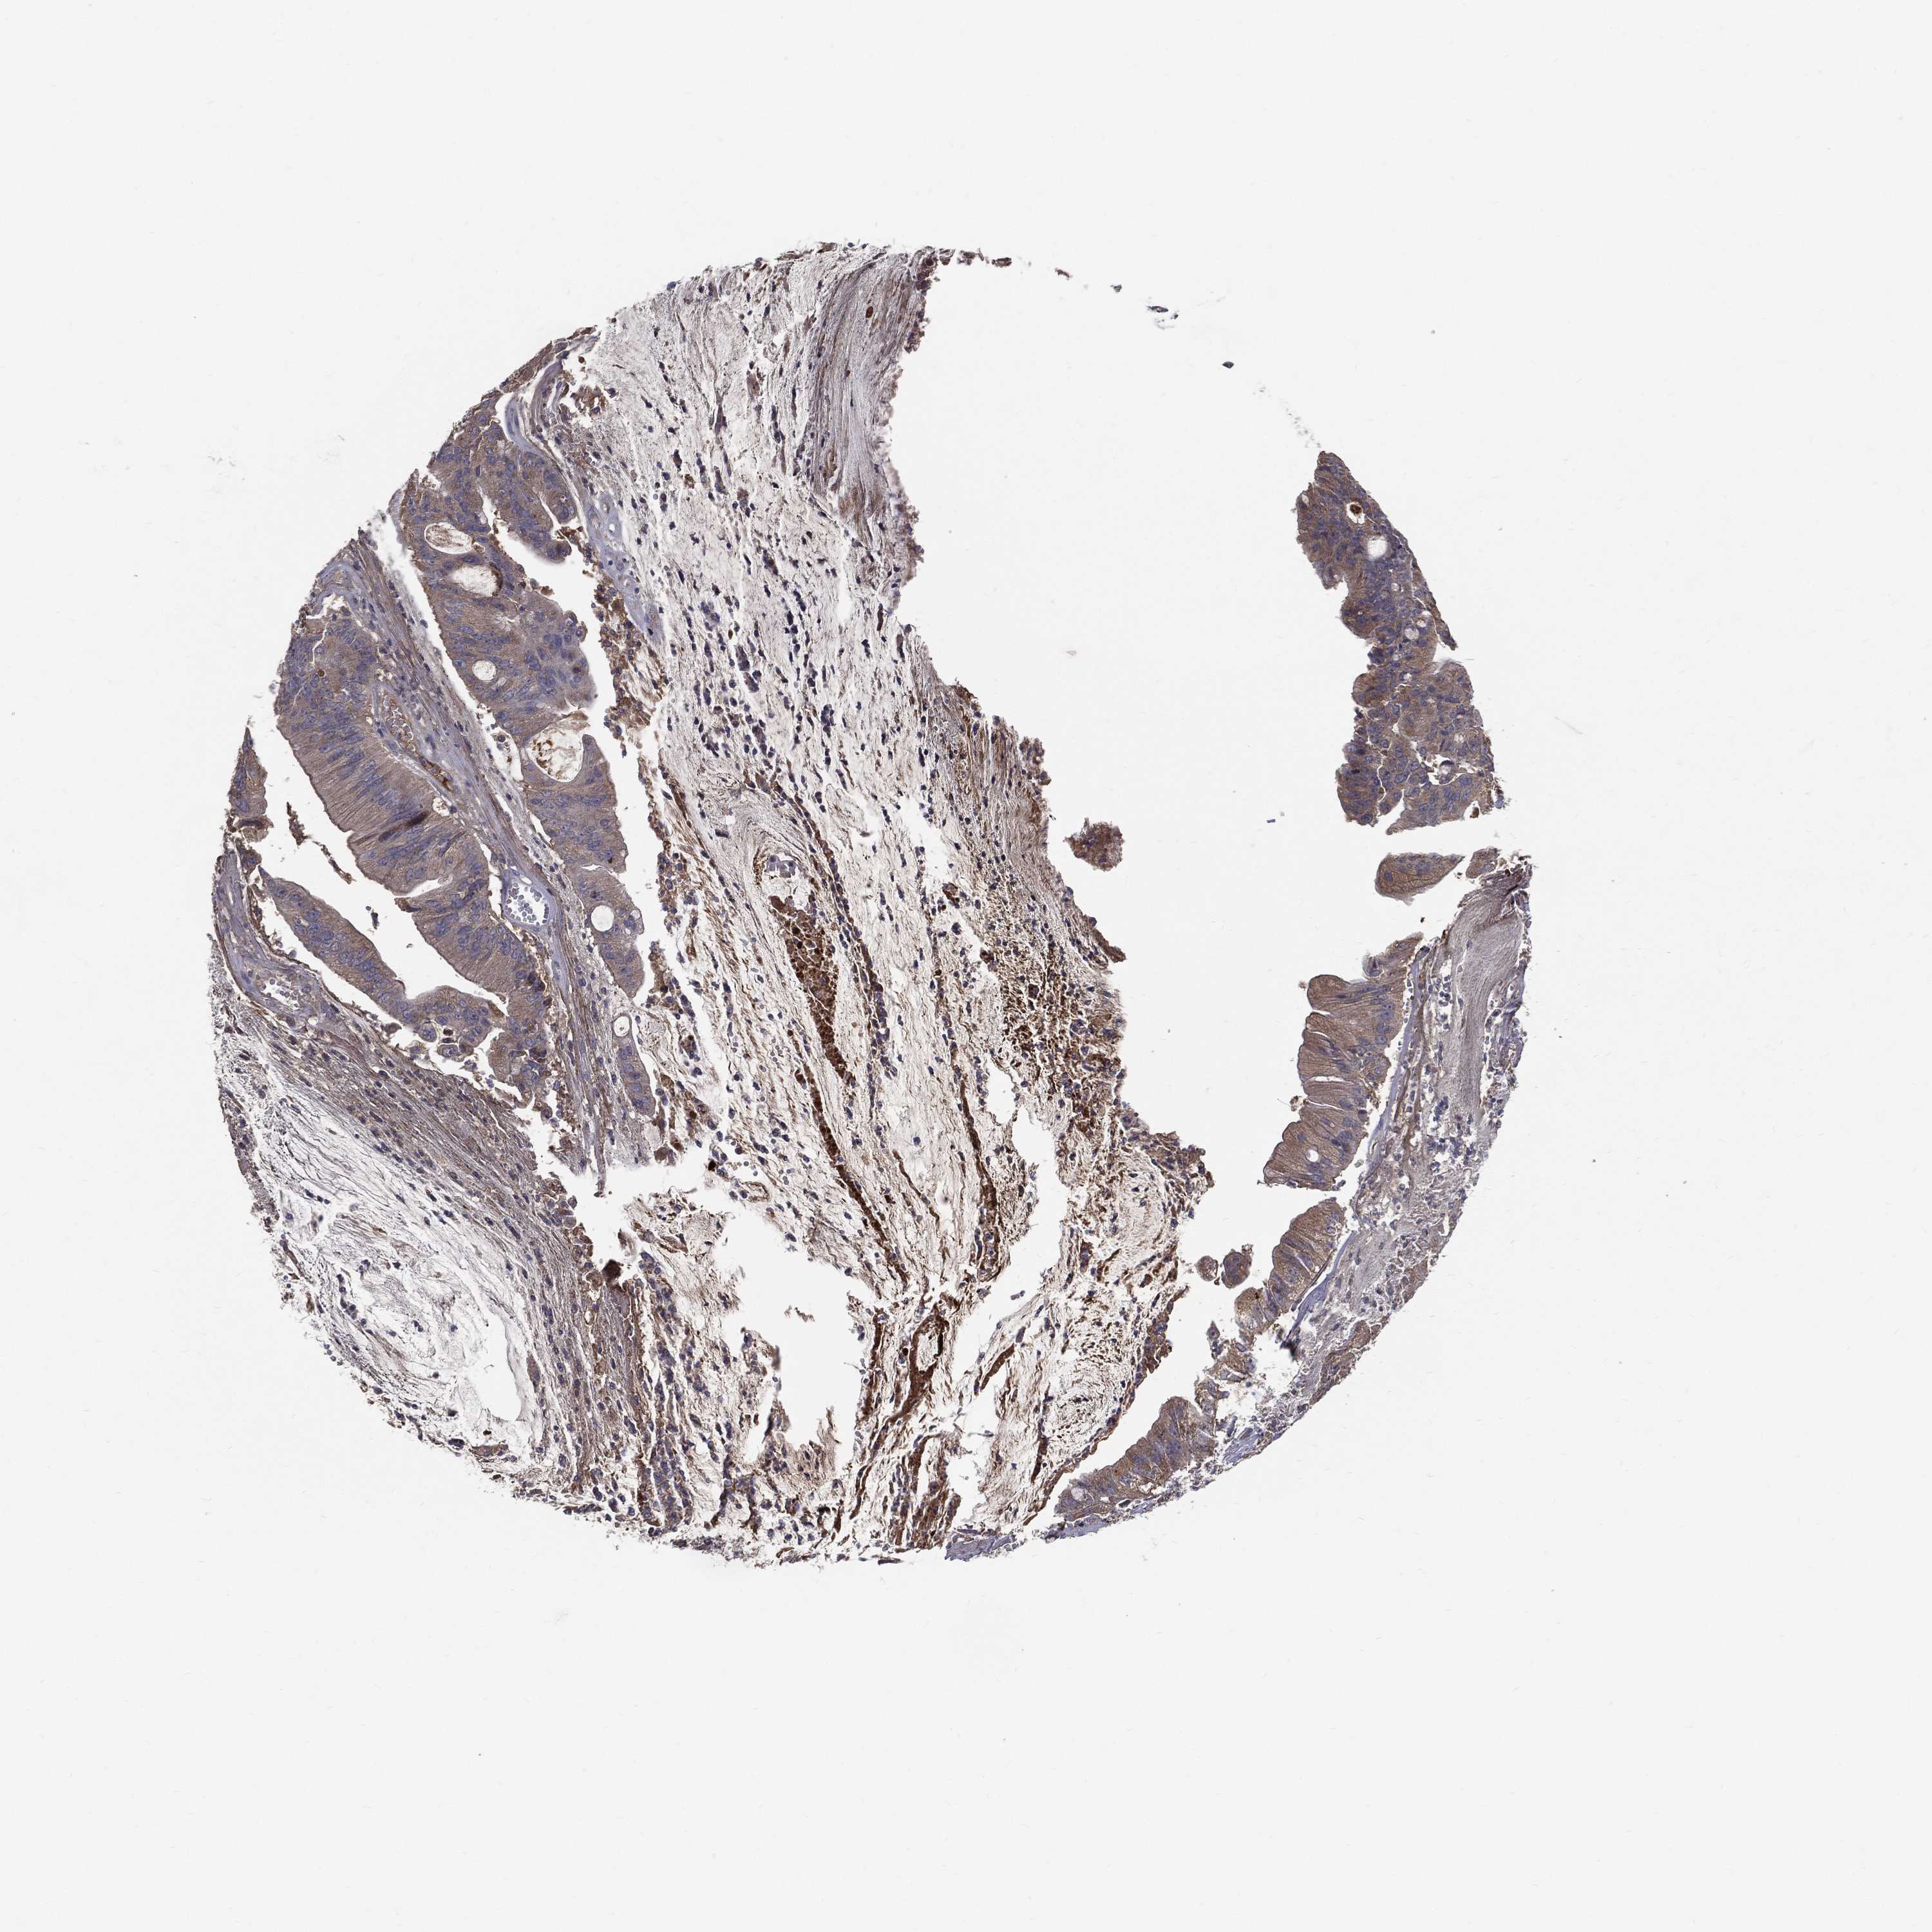

CANCER COLORECTAL CANCER Show tissue menu

Colorectal cancer

Human cancer

Colon adenocarcinoma

Rectum adenocarcinoma